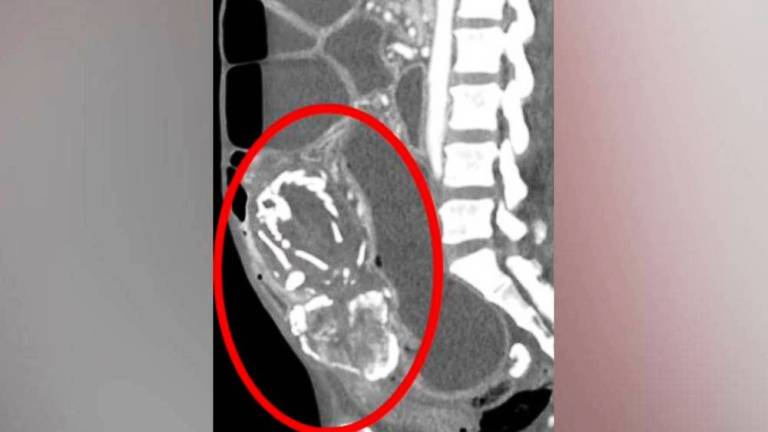

وقبل الوفاة بأيام زارت المرأة الطبيب تشكو من عسر هضم، وخلال الفحوص تم اكتشاف وجود جنين متحجر في بطنها، ضغط على أمعائها لفترة طويلة ومنعها من امتصاص الغذاء بشكل جيد ما أدى إلى وفاتها نتيجة نقص التغذية الحاد.

وقال أطباء في مستشفى جامعة ولاية نيويورك وفق صحيفة الخليج: “الخوف منعها من إجراء عملية لتدخل طبي تسبب لها في انسداد الأمعاء المتكرر ترتب عليه سوء التغذية الحاد أدى إلى الوفاة”.